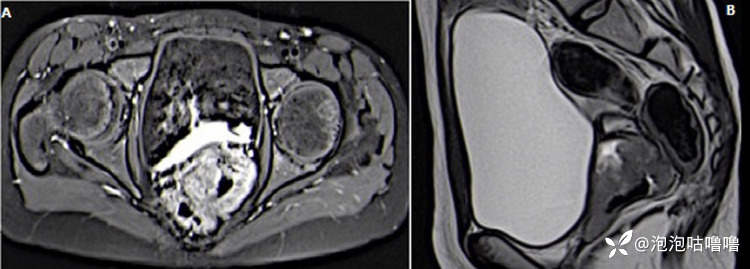

查体:鉴于女孩的年龄和缺乏合适的设备,阴道检查很困难。子宫附件彩超及 MRI显示宫颈阴道区域有一个大小为 5.1 x 6.2 x 6.5 厘米的异质肿块(图1)。没有肝或肺转移。肿瘤标志物(血清甲胎蛋白、β-人绒毛膜促性腺激素)未检测到。

图1A) T1 FAT SAT 对比 MRI 显示肿块占据阴道,且不均匀增强; B) 无对比的 T2 显示阴道肿块累及宫颈并涉及膀胱后侧